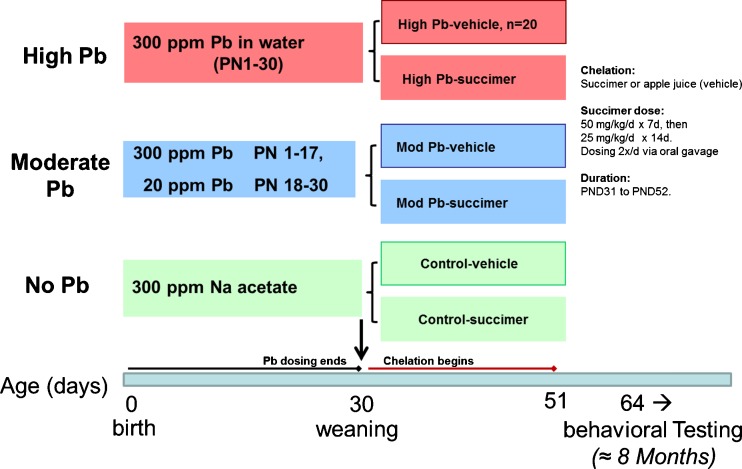

We present results from our published rodent studies to address this question [20, 21]. This study used a 3 × 2 factorial design with three levels of lead exposure (no lead, low lead, and high lead), crossed with two levels of succimer treatment (no succimer, i.e., the apple juice vehicle, or one 3-week succimer regimen; Fig. 13). The animals were lead exposed from birth until postnatal day 30 (pre-weaning exposure was via the lactating dam, post-weaning was via drinking water), followed by chelation, and then behavioral testing.

Fig. 13.

Study design and timing of testing in the rodent succimer chelation study (Stangle et al. [20]; Beaudin et al. [21]) [Stangle reproduced with permission from Environmental Health Perspectives; Beaudin reprinted from Neurotoxicology and Teratology with permission from Elsevier]

An extensive battery of behavioral tests, requiring approximately 8 months to complete, was administered. The tasks, which tapped a broad range of cognitive and affective functions, were similar in design and concept to tasks used with human subjects, to facilitate extrapolating the results to the target human population. We will focus mainly on a subset of the findings, specifically, the results from a series of visual discrimination and attention tasks.